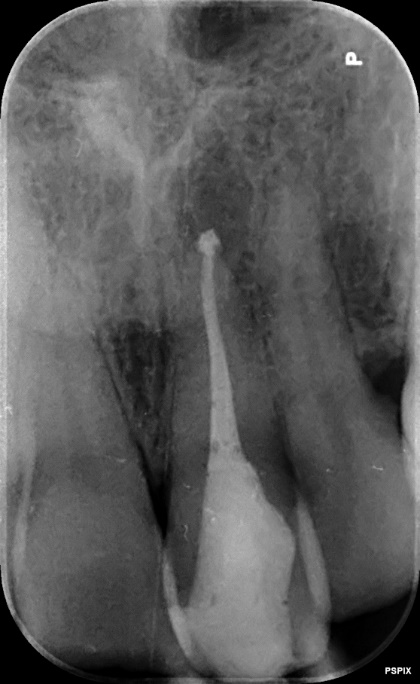

Upper Incisor trauma case primary root canal treatment and rebuild